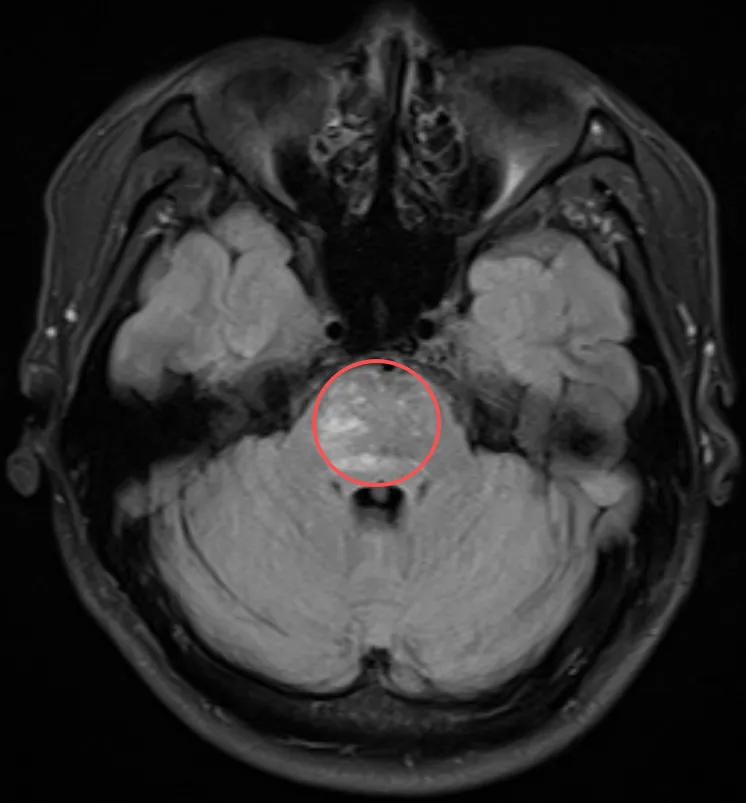

謝先生因頭痛偶然發(fā)現(xiàn)橋腦占位性病變——橋腦作為腦干的一部分,手術(shù)風(fēng)險(xiǎn)極大。此時(shí),他已出現(xiàn)間歇性頭脹、偶發(fā)耳鳴及腿無(wú)力感,好在并沒(méi)有明顯的癥狀。找了多位醫(yī)生,均建議保守觀察,現(xiàn)階段手術(shù)潛在風(fēng)險(xiǎn)太大,術(shù)后生活質(zhì)量可能下降,因此不建議手術(shù)。面對(duì)正處上升期的事業(yè)、幸福的家庭,謝先生充滿(mǎn)焦慮,下一步到底該如何做。恰逢巴教授來(lái)華,他獲得了這次面對(duì)面交流機(jī)會(huì)。

橋腦占位

橋腦占位影像

巴教授分析指出,謝先生的頭痛癥狀可能與當(dāng)前腦內(nèi)病灶并無(wú)直接關(guān)聯(lián)。此類(lèi)病例他在執(zhí)業(yè)生涯中近十年遇到一例,謝先生是其近十年來(lái)接診的第二位類(lèi)似患者。

教授進(jìn)一步提到,他曾接觸過(guò)病情相似的國(guó)外案例。那些患者最終選擇了開(kāi)放性活檢手術(shù),術(shù)后均未出現(xiàn)新的神經(jīng)功能障礙?;顧z組織被送至兩到三個(gè)中心進(jìn)行聯(lián)合會(huì)診,經(jīng)綜合評(píng)估后最終明確了病灶性質(zhì)。只有獲得確切的病理診斷,才能為后續(xù)治療提供清晰方向。

關(guān)于為何不推薦穿刺活檢,教授解釋道:穿刺僅能獲取極微量的組織樣本(例如0.5毫米),如此小的樣本量通常難以支撐全面、準(zhǔn)確的病理分析。此外,穿刺過(guò)程存在出血等風(fēng)險(xiǎn)。因此,教授更建議通過(guò)開(kāi)顱手術(shù)獲取足量標(biāo)本,為病理診斷提供可靠依據(jù)。

教授最后提出兩條建議:一是繼續(xù)保持臨床觀察;二是考慮通過(guò)手術(shù)方式進(jìn)行活檢,以獲取足夠病理組織明確診斷。他特別強(qiáng)調(diào),在未明確診斷前,不應(yīng)盲目進(jìn)行化療或放療。